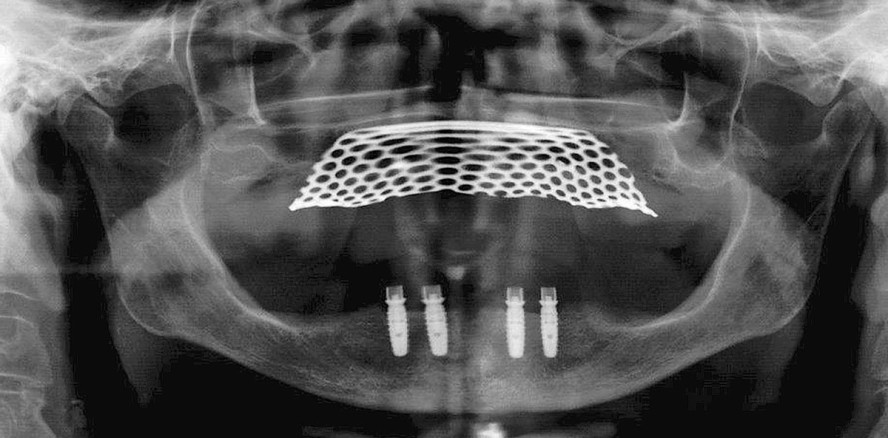

Aufgrund des geringen Knochenangebots im lateralen Unterkieferbereich (Abb. 2 und 3) wurde bei der Patientin eine Locator®-Versorgung auf vier intraforaminär inserierten Implantaten verankert. Es wurden vier iSy Implantate der Größe 3,8 mm Durchmesser und einer Länge von 11 mm inseriert.5,6 Die folgenden Abbildungen (Abb. 5–9) zeigen das protokollgerechte chirurgische Vorgehen nach dem iSy Konzept.